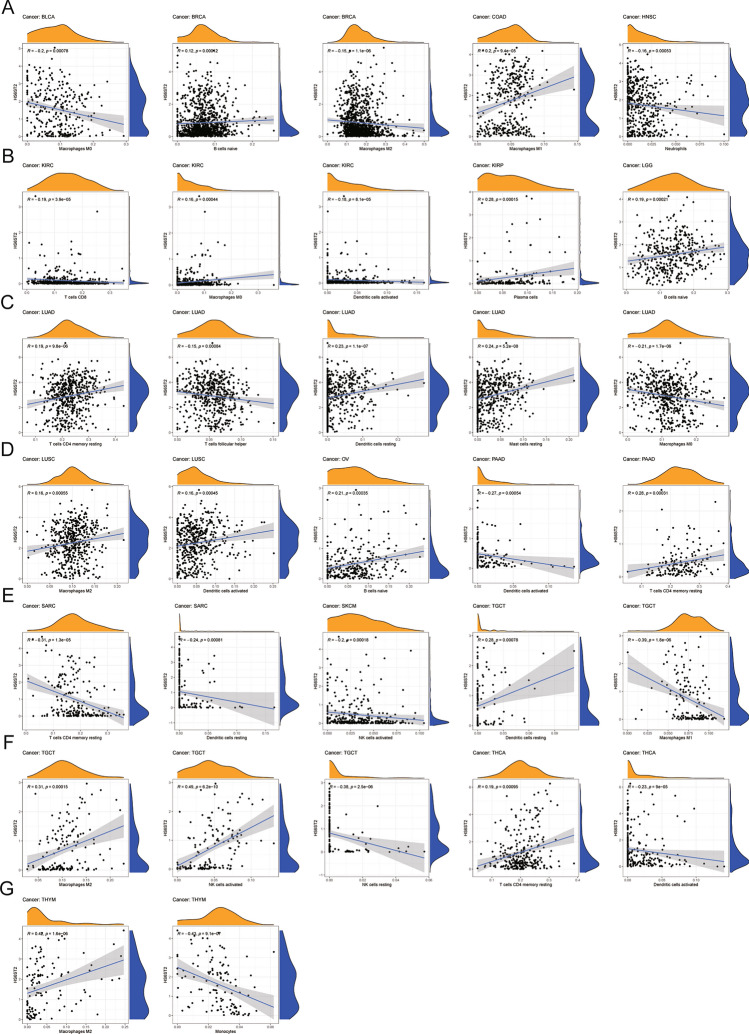

Association between the levels of tumor-infiltrating immune cells and HS6ST2 expression

The association between HS6ST2 expression and the levels of 22 different tumor-infiltrating immune cells was then studied. HS6ST2 was found to be significantly linked with the infiltrating levels of naive B cells across cancers in the TCGA data, particularly in breast invasive carcinoma, brain lower grade glioma, and ovarian serous cystadenocarcinoma (Supplementary Table S1). In lung squamous cell carcinoma, testicular germ cell tumors, and thymoma, the number of M2 macrophages penetrating a tissue was strongly linked with HS6ST2 expression; however, in breast invasive carcinoma, the correlation was negative. We also examined the relationships between HS6ST2 and the levels of infiltrating T cells and natural killer (NK) cells in 33 cancer types. The level of infiltrating resting CD4 memory T cells was favorably correlated with HS6ST2 expression in lung adenocarcinoma, pancreatic adenocarcinoma, and thyroid carcinoma but inversely correlated with HS6ST2 expression in sarcoma. Furthermore, HS6ST2 was favorably connected with the level of activated NK cells activated in testicular germ cell tumors but inversely correlated with the level of activated NK cells in skin cutaneous melanoma. Figure 9 displays the correlations between HS6ST2 expression and the numbers of various types of invading immune cells in various cancers. Our results suggest that HS6ST2 may enhance immune system evasion by making it easier for immune cells to infiltrate tumors.

According to our findings, HS6ST2 also plays a crucial role in cancer immunity. The TME is important for cancer progression and therapeutic response33. HS6ST2 expression was found to be inversely related to stromal and immune cell composition in the TME in LUSC, BLCA, and LGG, but not in THCA, as measured by ESTIMATE scores. Immune cells that invade tumors play an important role in maintaining stability within the TME and in the development and treatment of cancer36,37. The TME contains a large number of M2 macrophages, and naive B cells may provide support for tumor growth38,39. HS6ST2 had a positive relationship with the levels of M2 macrophages cells and naive B cells in many malignancies. Those findings may explain the function of HS6ST2 as a risk factor in the majority of tumor types. In addition, our research confirmed the coexpression of HS6ST2 with genes related to immunological function. The HS6ST2 expression level was significantly connected with immune-related genes involved in tumorigenesis but was negatively correlated with CXCR3 and HLA-F40,41. All of these findings suggest that modulating HS6ST2 expression may also be a viable method for improving immunotherapy outcomes.